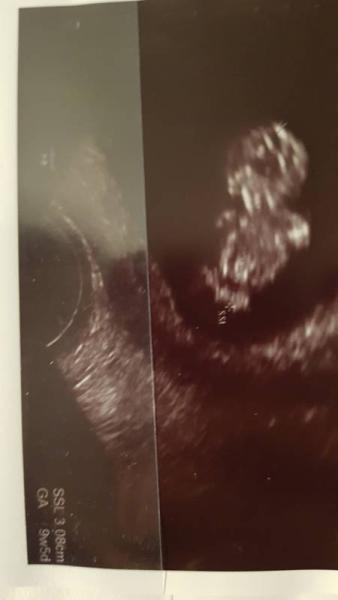

Hallo ihr Lieben Ich habe mich ja die letzte Zeit zurückgezogen. Was aber nicht an Euch sondern an meinem Gesundheitszustand lag. Erst hatte ich einen Harnwegsinfekt wogegen ich ein Einmalantibiotika bekam. Leider wirkte das bei mir nicht und ich bekam ein anderes Antibiotikum. Da durch bekam ich dolle Durchfall, entweder kam es durch die Übelkeit oben raus oder unten. Mir ging es sehr schlecht und ich habe ständig Elektrolyte getrunken. Als wenn das nicht alles genug wäre, bekam ich einen Pilz ( wegen Antibiotikum). Der war so heftig, dass ich eine kortisonhaltige Pilzcreme bekam. Heute war ich dann nochmal beim FA, Urin ist gut und Pilz auch weg. Weil ich mir Sorgen machte wegen den ganzen Medikamenten, würde noch ein US gemacht. Unser Bauchbewohner ist ein Tag weiter und hat die ganze Zeit sich bewegt, so süß. Die Ärztin lachte und meinte, dass Baby ist ein kleiner, aktiver Tänzer. Sah wirklich aus als wenn es tanzen würde . Es war so unbeschreiblich schön.

Bild zu Ich bin wieder da mit guten Neuigkeiten  - Forum für April - Mamis